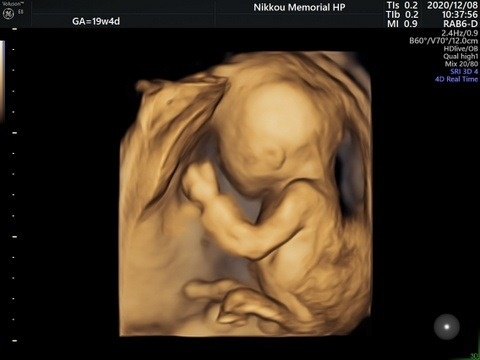

当科は、札幌医科大学産婦人科教室からの派遣医引き上げに伴い、2024年7月より分娩取り扱いの一時停止を余儀なくされました。しかし、2024年10月に道外から周産期専門医一名が新たに着任し、昭和大学横浜市北部病院産婦人科教室のご協力も得て分娩を再開することができました。これまで同様、西胆振地区唯一の周産期センターとしてハイリスク妊産婦や未熟児の管理とともに、助産師による妊産婦さんの立場に立った細やかなケアを、地域の皆様に提供してまいります。また、胆振地区唯一となる無痛分娩の提供も行っております。